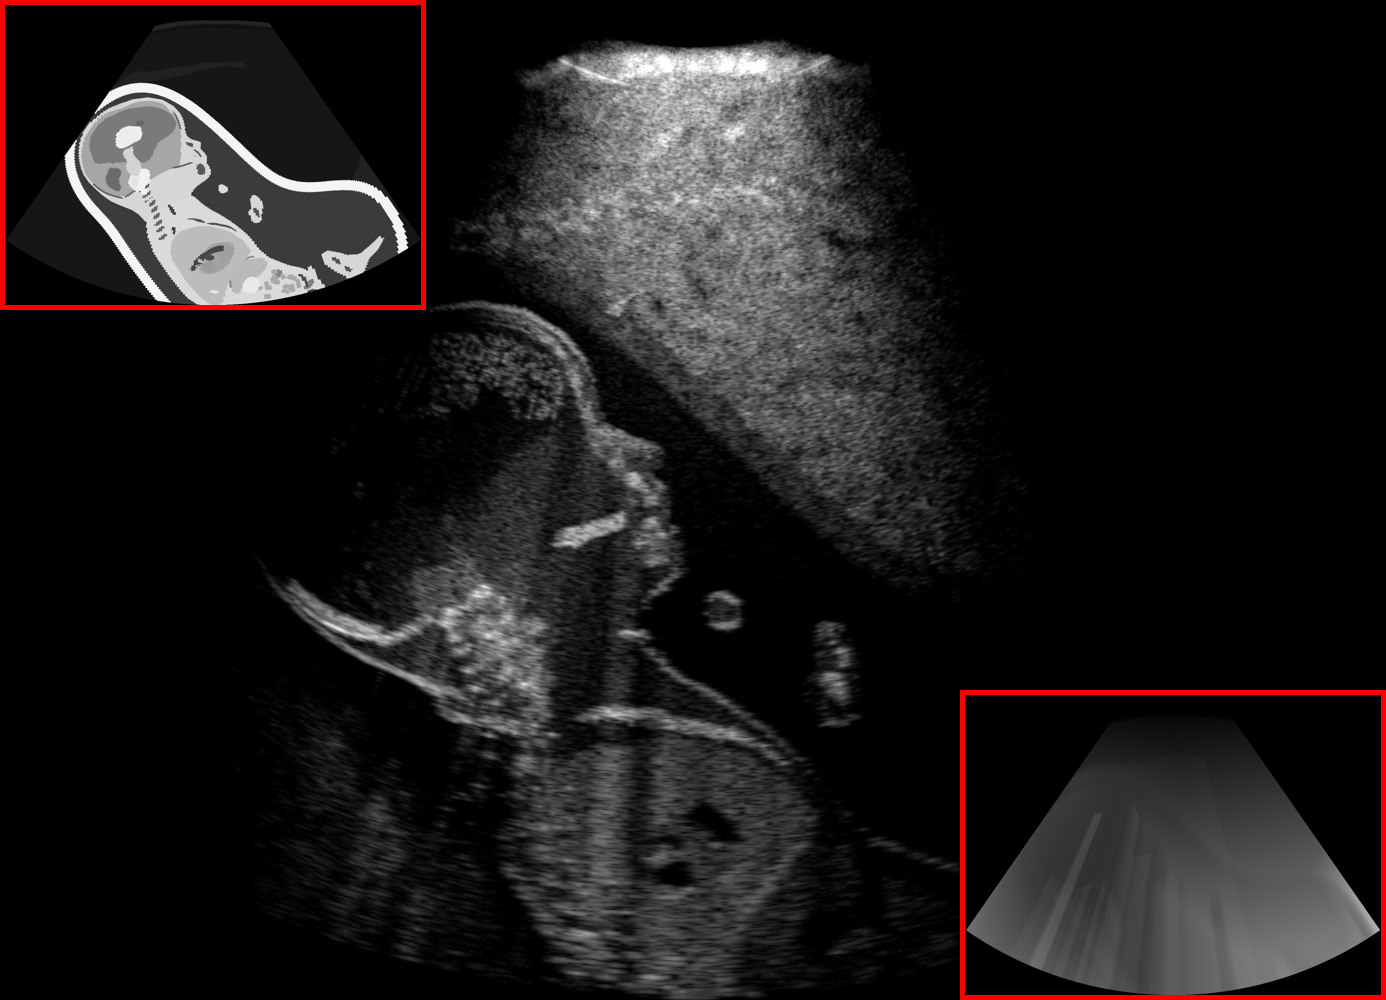

Qualitative evaluation.

Fig. 2 depicts the qualitative results for all the models mentioned above, with arrows pointing at structures relevant to discussion points below. The visual results of the ablated variants of SA2H show substantial quality degradation compared to the full SA2H model, demonstrating the importance of each proposed architectural contribution. Given only segmentation map in the network input, SA2H-att fails to generate acoustic shadows, e.g. those cast by the ribs. Detailed structures such as the cervical vertebrae are blurred out in the SA2H-concat results, which also contain hallucinated structures mainly due to insufficient preservation of input information along the encoding-decoding path. With SA2H-conv, checkerboard artefacts are observed due to the lack of proposed additional stride-1 convolutional layers. SA2H-noise without any explicit noise input is seen to be sub-optimal at generating textural details. The baseline method NSA2H fails to preserve anatomical structures and acoustic shadows in all cases, while the simulated textures also show significant artefacts such as checkerboard patterns. Realism of different simulation aspects may become relevant given different clinical applications and scenarios. For instance, improved structural preservation, e.g. with the hyperechoic bony structures such as the skull and the ribs, of the final model over its ablated variants and NSA2H may prove relevant in fetal head measurements, while the textural improvements facilitating screening fetal organ maturity, e.g. lungs. Compared to the silver-standard model LSA2H with a low-quality rendered image as additional input, SA2H is seen to be on par in structural preservation. Note that shadowing on homogenous regions (e.g. the rib shadowing on the homogenous lung region on the 4th column of Fig. 2) with our proposed method SA2H is represented more faithfully compared to LSA2H, whereas shadows on structurally complex regions (e.g. the skull shadowing around the heart and surrounding tissues on the 3rd column of Fig. 2) are suboptimal with our SA2H. Therefore, one may have to evaluate our method given particular simulation tasks, e.g. its clinical validity for fetal heart exams. However, even with low quality rendered images, LSA2H leads to artificial enhancements of intensities, lack of acoustic shadows, and low-quality textures especially near the probe, for which SA2H yields satisfactory results as illustrated in Fig. 2.

(a) Target

(b) SA2H

(c) SA2H-att

(d) SA2H-concat

(e) SA2H-conv

(f) SA2H-noise

(g) NSA2H

(h) LSA2H